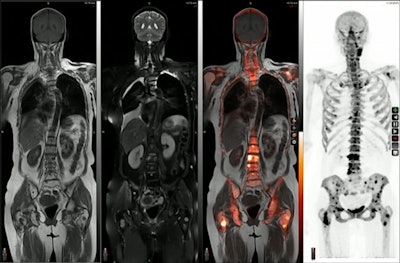

Both PET and MRI scanners are used in cancer imaging, with PET/MRI hybrid scanners developed about 12 years ago. These scanners can provide almost simultaneous detailed tumor assessments from multiparametric MRI with complementary physiologic information from PET. Thus, when images are fused -- essentially overlaid on one another -- by software during processing, the approach provides diagnostic value for clinicians not possible with either approach alone. Several studies support the role of PET/MRI for cancer evaluation, he noted.

To illustrate the value of PET/MRI, Chandarana presented a case of a woman with cervical cancer. Initially, she underwent an MRI exam that suggested the cancer had spread beyond her cervix. A CT scan was also performed, with inconclusive results. Ultimately, a PET/MRI was performed, which provided the details necessary for surgery staging.

The example illustrates the concept of the "one-stop-shop" approach -- with a single PET/MRI session (which also can be done quicker and with lower radiation doses, Chandarana noted) potentially replacing the two separate imaging exams in these cases, he said.